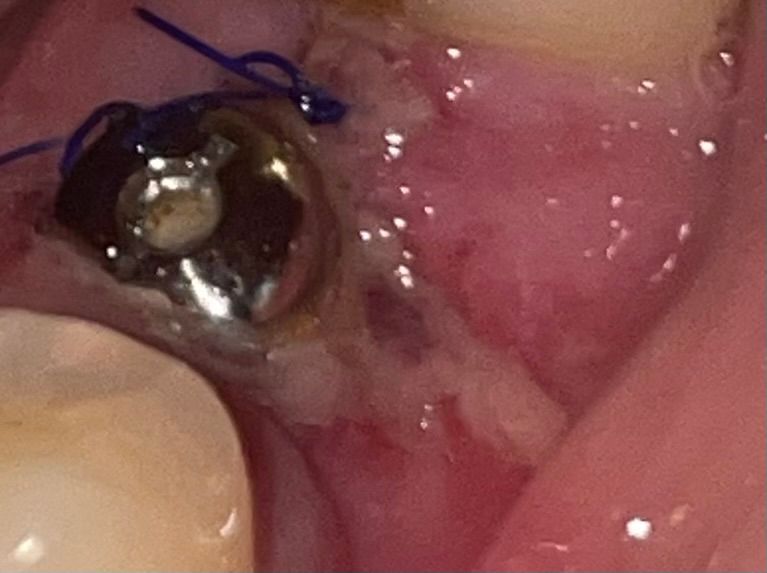

1월 26일 오후에 발치 후 픽스처 식립하고 슈처까지 했는데 잇몸이 잘 아물고 있는걸까요 ?

통증이나 불편한 건 없는데 잇몸에 하얗게 생긴 것 같고 사진 흰 부분이 멍 든 것 같이 보이는게 슈처 후 아무는 단계인지 뭔 지 궁금 합니다ㅠ

사진상 치유과정에 있어서 특별히 문제점은 보이지 않고 적절히 치유가 이뤄지고 있는 것 같습니다